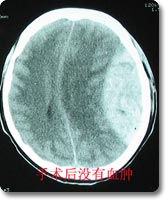

颅脑损伤的综合治疗

神经外科治疗各种颅脑损伤病人已有50余年历史,拥有一支高素质的专业医护队伍,先后收治各类颅脑损伤病人7000余例,尤其是在严重颅脑损伤的抢救方面,已总结出一整套抢救治疗方案,积累了丰富的救治经验,救治成功率高于文献报导的平均水平,死亡率、残废率低。